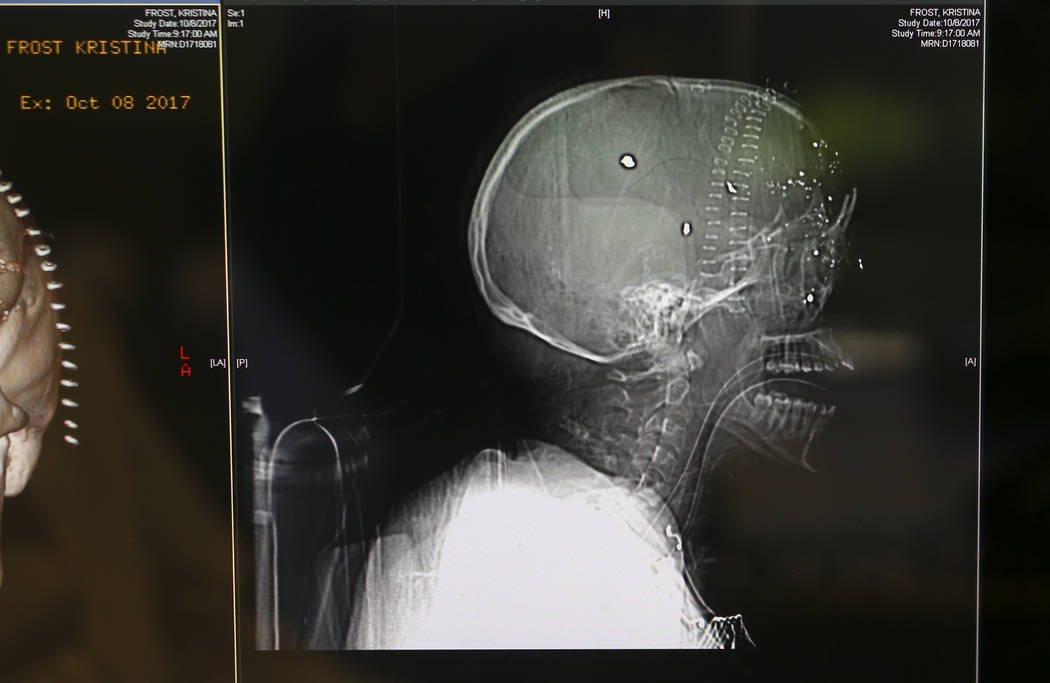

One of the head shot victims, who arrived in the back of a pickup truck, was Tina Frost, a 27-year-old Maryland native and San Diego transplant who was attending the Route 91 Harvest festival with her boyfriend. A bullet entered the certified public accountant’s right eye and damaged her brain to an extent that remains unclear, leaving her in a coma in Sunrise’s intensive care unit.

Blum said that after making an incision from one ear to the other and peeling her scalp back, he could see the extent of the damage and how it shattered bones in the front of her skull and forehead, injuring the frontal lobes of the brain.

He saw no alternative but to remove Frost’s damaged right eye. Then he removed as many of the bullet fragments and shrapnel as possible and cut a section of bone from her skull to give the brain room to swell.